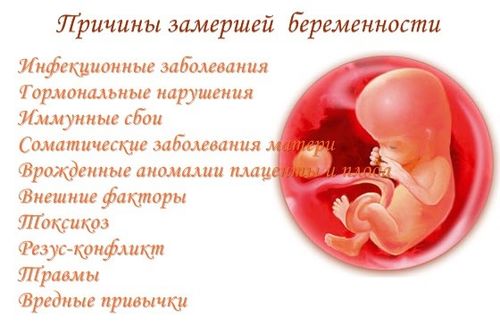

Причины замершей беременности при беременности

Причин остановки беременности в развитии очень много, часто врачам так и не удается установить причину, по которой то или иное вынашивание перестало развиваться. Также, это зависит от срока – причины замирания на ранних сроках иные, чем на поздних. В ходе исследований выявлены группы риска – те категории будущих мам, у которых вероятность замирания гораздо выше:

- Зачатие наступило в результате экстракорпорального оплодотворения.

- Будущей маме более 35 лет.

- Наличие инфекционного и/или вирусного заболевания (ВПЧ, герпеса).

- Вредные привычки – курение, прием алкогольных напитков. Вредно употребление алкоголя и курение не только во время вынашивания, но и на протяжении длительного времени перед зачатием.

- Генетическая предрасположенность – ранее уже фиксировались замирания у матерей, бабушек, сестер женщины, или у нее самой в предыдущих беременностях.